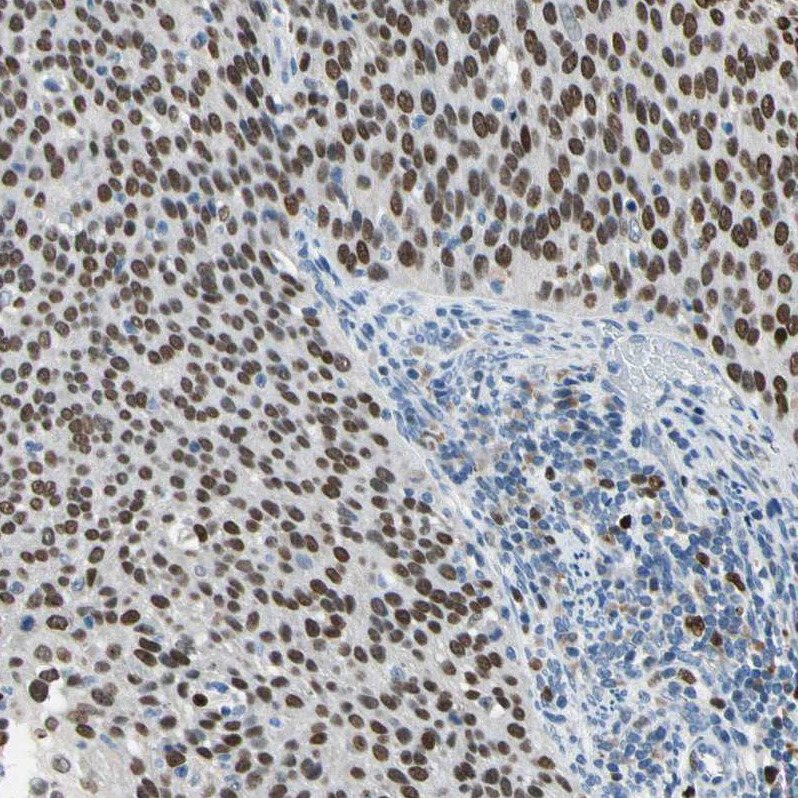

Immunohistochemical staining of human Cervical cancer shows strong nuclear positivity in tumor cells.